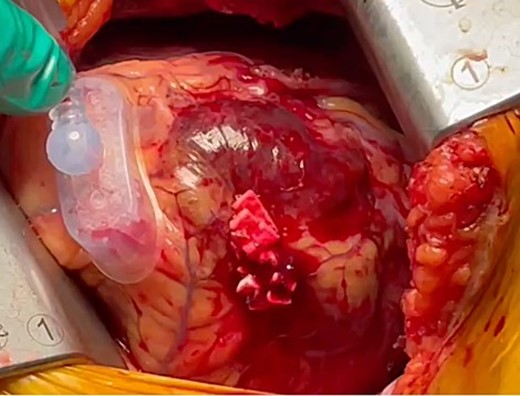

The patient was positioned by elevating in a 30° to 40° right lateral decubitus position to facilitate a widened intercostal space. The patient was intubated with a double-lumen endotracheal tube. A 10 cm left mini-thoracotomy was performed in the fourth intercostal space, with 1/3 of the incision medial to the mid-clavicular line. The ThoraTrak® MICS Retractor System (Medtronic Inc., MN, USA) was employed to achieve optimal access to the left chest and effectively visualize the internal mammary arteries. The LITA was harvested in a skeletonized fashion under direct vision, and the saphenous vein (SVG) was harvested from the right leg. To maintain the activated clotting time > 280 s, heparin (1 mg/kg) was administered after the LITA harvest. In this case, the Tentacles NEO (Sumitomo Bakeride, Akita, Japan) was used as a heart poisoner and cardiac stabilizer. We made four distal anastomoses (LITA-LAD, Aorta-SVG1-first diagonal, Y-composite SVG2-OM- posterolateral artery). When one of the suction cups attached to the apex of LV was detached, an epicardial hematoma was coming at the attachment site (Fig. 2). This bleeding point was repaired by continuous suture by 4–0 prolene with two big felt. After protamine was given, good hemostasis was achieved (Fig. 3).

We observed an epicardial hematoma at apex of the left ventricular when we detached one of the Tentacles NEO suction cups.